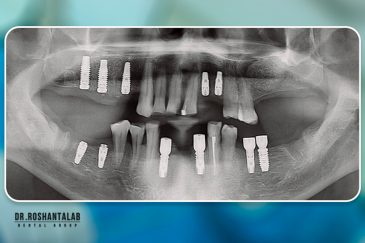

انتخاب بهترین متخصص ایمپلنت که به تکنیکهای روز دنیا مسلط باشد، تضمینکننده سلامت فک و زیبایی لبخند شماست. در کلینیک دندانپزشکی دکتر روشنطلب، ما با بهرهگیری از تجهیزات دیجیتال در ۵ شعبه فعال (تهران، اصفهان، رشت و استانبول ترکیه)، خدمات تخصصی کاشت ایمپلنت دندان را برای بیمارانی که کیفیت و دقت برایشان اولویت دارد، ارائه میدهیم. در این متد، پروسه درمان با ظرافت بالا انجام شده؛ راهکاری ایدهآل برای کسانی که به دنبال درمان بدون درد با بالاترین نرخ موفقیت هستند.